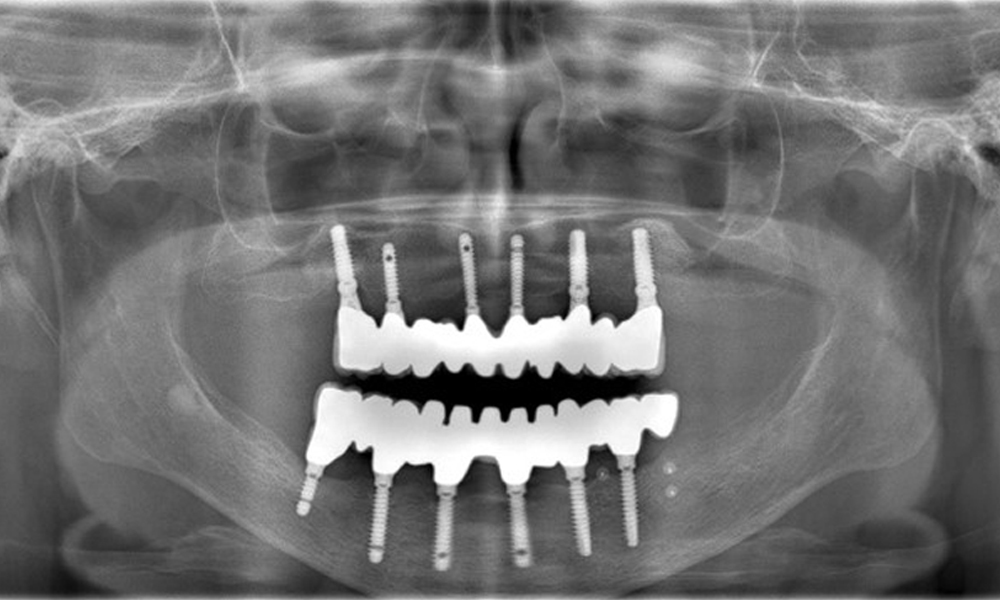

The radiographic images reveal bone resorption.

Figure 2: The radiographic images reveal bone resorption.